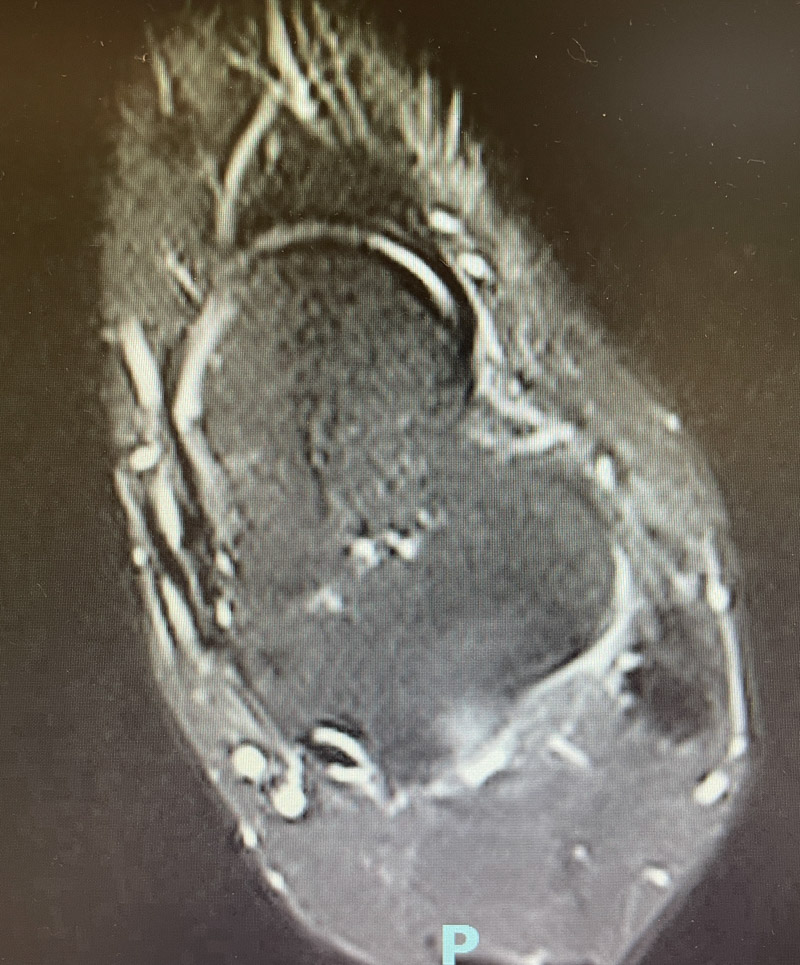

▲距腓前韌帶撕裂

“大家總是認為,踝關節扭傷,休息休息就好,其實,有可能是踝關節距腓前韌帶撕裂所致的關節失穩。”韋釗嵐說,“踝關節扭傷在關節及韌帶損傷中是發病率最高的疾病,占所有運動損傷的40%左右,而踝關節的穩定性對于日常的活動和體育運動的正常進行起重要作用,是絕對不可小覷的。如果腳踝第一次扭傷時未得到及時診治,容易引起經常性的反復扭傷。扭傷不僅造成軟骨的撞擊,包括增生的疤痕組織等,也會造成關節的撞擊,產生撞擊綜合征,造成關節反復的腫痛與不適。”